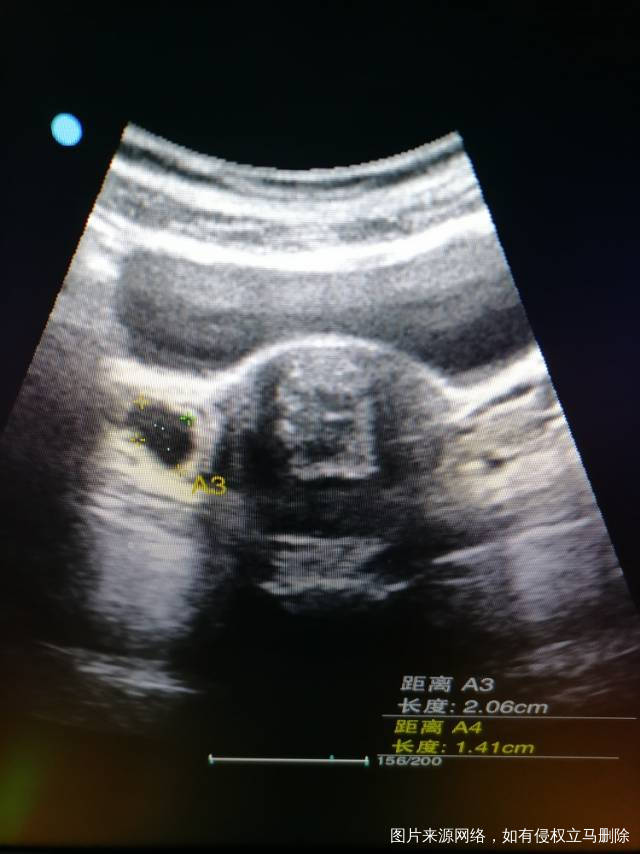

20号应该来月经,5号查的卵泡2.0×1.4cm,6号下午查变成3.4×2.5cm,晚上9点感觉肚子疼,7号早上查彩超卵巢里面什么都没有,周围全是水